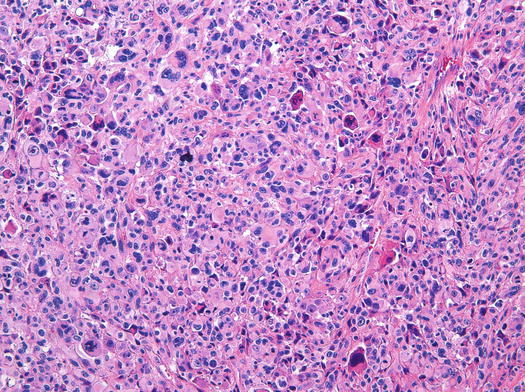

Rhabdomyosarcoma - MyPathologyReport.ca

www.mypathologyreport.ca

www.mypathologyreport.ca

rhabdomyosarcoma